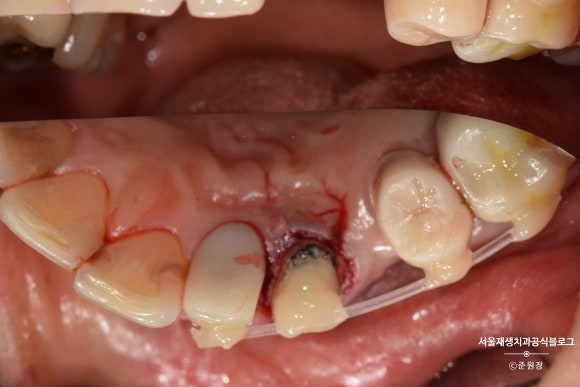

연세가 조금 있으셨음에도 불구하고,

2주 후에 다행히 치아가 뼈에 단단히 결합된 상태로 재내원하셨습니다.

와이어를 제거했습니다.

최소한의 길이가 확보되긴 했지만 아직 크라운을 씌울 정도의 충분한 부피는 아닙니다.

나머지는 포스트와 레진의 도움을 받아 쌓아올립니다.